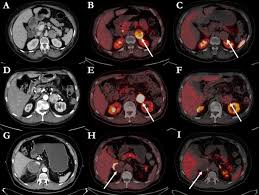

An F-DOPA PET scan is a specialized imaging test designed to study dopamine activity in the brain. It plays a crucial role in diagnosing conditions such as Parkinson’s disease, movement disorders, certain neuroendocrine tumors, and complex neurological symptoms. The reason many people look for Affordable F-DOPA PET Scan Services is because the tracer used—called F-18 DOPA—is highly specialized, and the process requires advanced nuclear medicine technology.